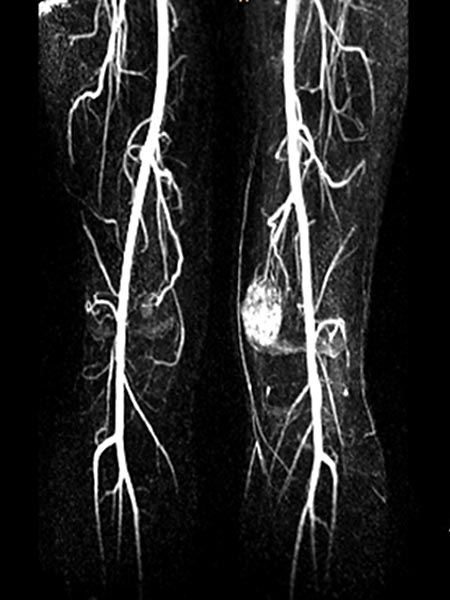

Die kontrastmittelgestützte MR-Angiographie noch in einer frühen, arteriellen Phase zeigt dann eine frühe, starke arterielle Vaskularisation der venösen Malformation, als Hinweis auf deutliche arteriovenöse Fisteln in der venösen Malformation.